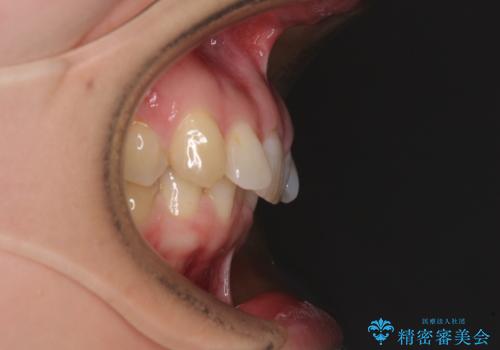

奥歯の咬み合わせを見ると、上顎が下顎に対して相対的に前方にありました。

深い咬み合わせを改善するためには、上顎臼歯を後方に移動させつつ、下顎の小臼歯を直立させる必要があります。